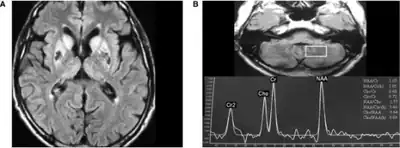

Neuroferritinopathy is most commonly diagnosed using MRI and other neuroimaging techniques.[1] MRIs help identify the iron deposits in the cerebellum, basal ganglia, and motor cortex common to neuroferritinopathy.[8] MRIs of affected individuals also show mild cerebellar and cerebral atrophy, or tissue breakdown, and gas cavity formation in the putamen.[8] Most importantly, the MRIs show misfolded ferritin proteins and iron deposits in the glial cells of the caudate, putamen, globus pallidus, cerebral cortex, thalamus, and purkinje cells, causing neuronal death in these areas.[8]

a)High signal caudate and lenticular nuclei b) long echo time in deep left cerebellum